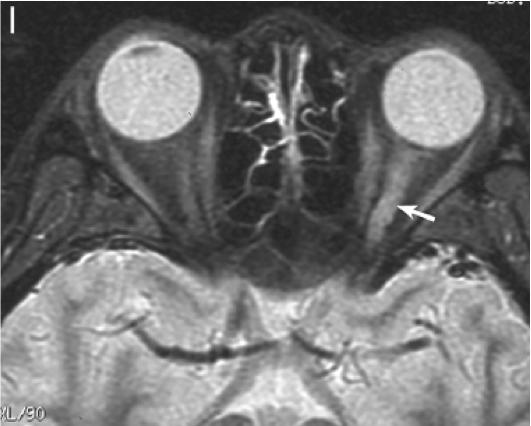

2. NMOSD 视神经MRI:病变较长,累及视交叉